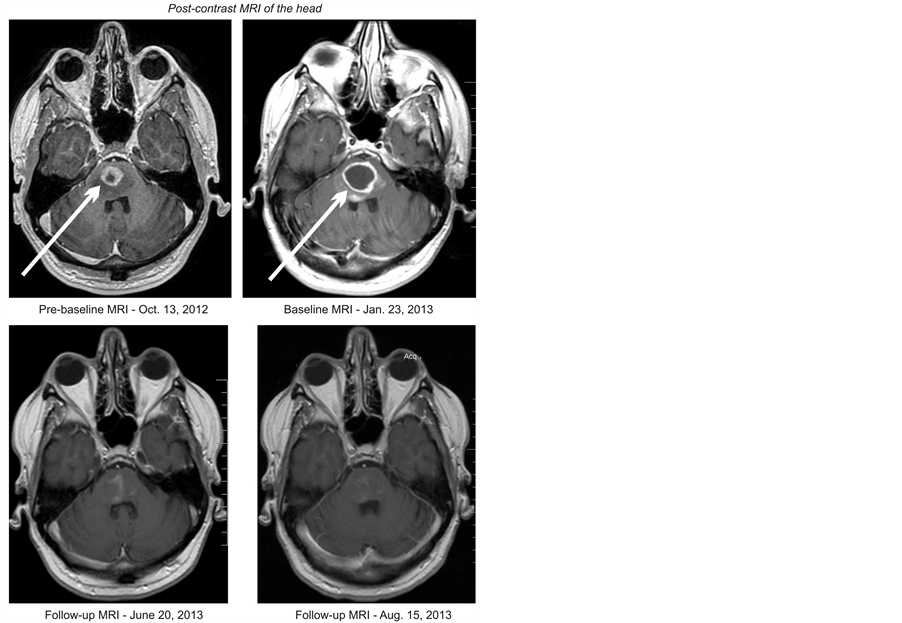

The patient accomplished reduction and finally, elimination of his neurological symptoms. He had temporary improvement of his left hemiplegia after 5 days and significant improvement after 5 weeks of treatment. He was symptom-free after 9 months. MRI of the head on March 11, 2013, revealed approximately 60% decrease of the contrast-enhancing tumor. The follow-up MRI of June 20, 2013 showed an 82% decrease of the tumor (Figure 1). On May 28, 2014, the tumor began to increase, but was still 53% smaller than baseline. The patient decided

Figure 1. Pre-baseline (before radiation), baseline (after radiation), and follow-up (on treatment at Burzynski Clinic) MRIs of the head, which illustrate a decrease in tumor size.

to discontinue the medications on July 25, 2014. A month later, he opted to start treatment with temozolomide (TMZ) for one month. Unfortunately, his disease progressed and he passed away on September 28, 2014.